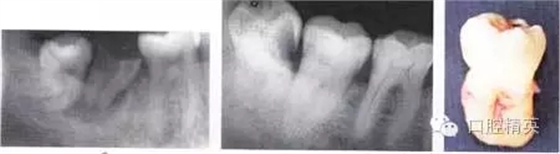

圖6-4 以上類(lèi)型的下頜第三磨牙由于根阻力大,一般需要分根才能拔除

A.多根牙 B。超長(zhǎng)根 C。牙根向遠(yuǎn)中彎曲 D。兩根環(huán)抱 E。根分叉大 F,根端肥大 G。彎根 H.U型根(X線片及離體牙)